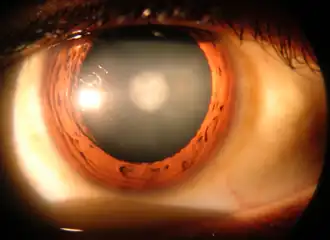

Диабетическая катаракта